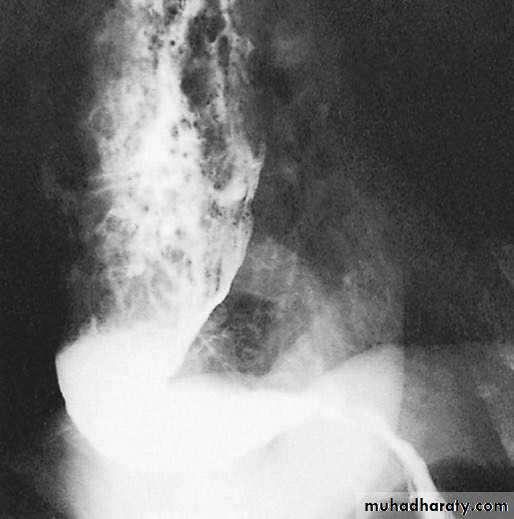

Figure2: Squamous cell carcinoma of the oesophagus producing

an irregular stricture with shouldered marginsClinical features: